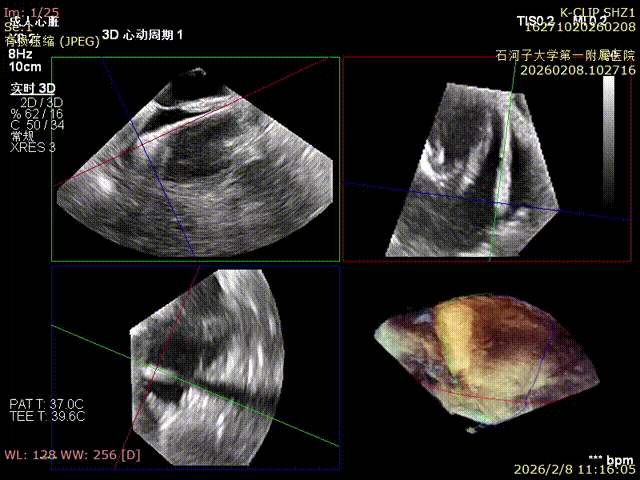

Preoperative anteroseptal regurgitation

Preoperative 3D view of regurgitation

Preoperative TTE: 4-chamber view regurgitation